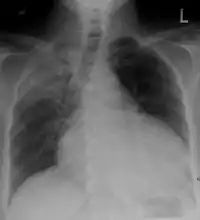

A pericardial effusion due to pericarditis

Chest x-ray: is non-specific and may not help identify a pericardial effusion but a very large, chronic effusion can present as "water-bottle sign" on an x-ray, which occurs when the cardiopericardial silhouette is enlarged and assumes the shape of a flask or water bottle.[2] Chest radiograph is also helpful in ruling out pneumothorax, pneumonia, and esophageal rupture.